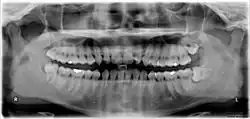

Zahn 28: Distale Zahnfleischtasche.

Zahn 38: Verlagerter Weisheitszahn mit „Schmutzwinkel“ zwischen den Zähnen.

Zahn 48: Ebenfalls distale Zahnfleischtasche.

A = Retinierter Weisheitszahn 48 mit mesialer Karies;

B = distale Karies am Zahn 47, dazwischen Gingivitis;

C = entzündete, künstliche Zahnfleischtasche;

D = Elongierter Zahn 18